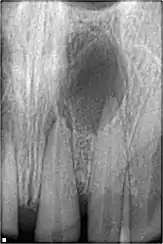

Résection apicale

Les objectifs de la résection apicale sont :

- retirer une partie de la racine qui ne pourrait être désinfectée ou/et remplie avec un matériau de remplissage de canal et dont les contenus peuvent avoir causé ou maintenu une inflammation,

faciliter l'accès pour la création d'une préparation de terminaison radiculaire, en vue d'un remplissage de terminaison radiculaire. L'apex doit être réséqué avec peu ou pas de biseau. Le procédé lui-même est rarement utilisé, et seulement quand on a considéré que le canal radiculaire a été traité de façon satisfaisante, et bien rempli.